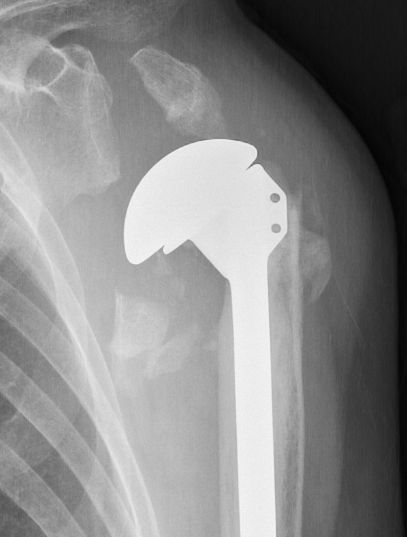

Hemiarthroplasty

Indications

Unreconstructable fracture - 4 part, comminuted, head spltting fracture

Insufficient glenoid

Patients too young for rTSA

Technique

Prosthesis

Remove and size anatomical neck

- identify diameter and thickness

- ream humerus and trial stem

Humeral height

- trial with arm hanging to replicate weight

- will usually need to leave stem proud from fracture

- should be able to anatomically restore tuberosities

- cement stem with retroversion of 30o

Repair tuberosities to the humeral stem